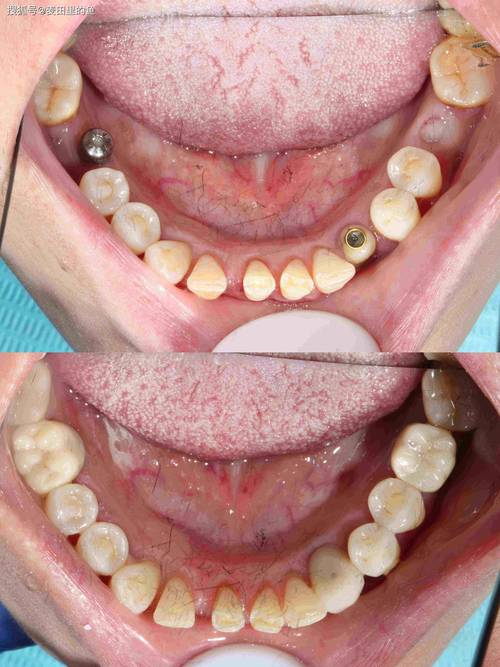

为缩短缺牙时间,部分患者选择“拔即种”(拔牙后立即种植),但若拔牙窝骨壁不完整(如邻牙倾斜导致骨壁缺损)、骨量不足或存在感染,需同期植骨填充间隙,提高种植体初期稳定性。